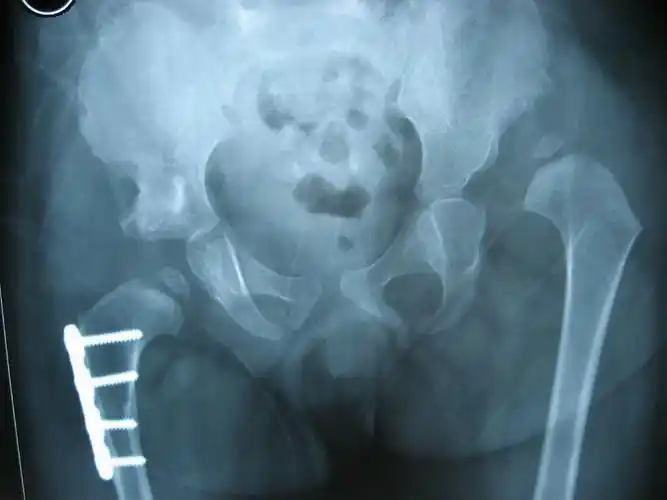

发育性髋关节发育不良ddh中老年人屁股疼痛的定时炸弹

先天性髋关节发育不良

发育性髋关节发育不良